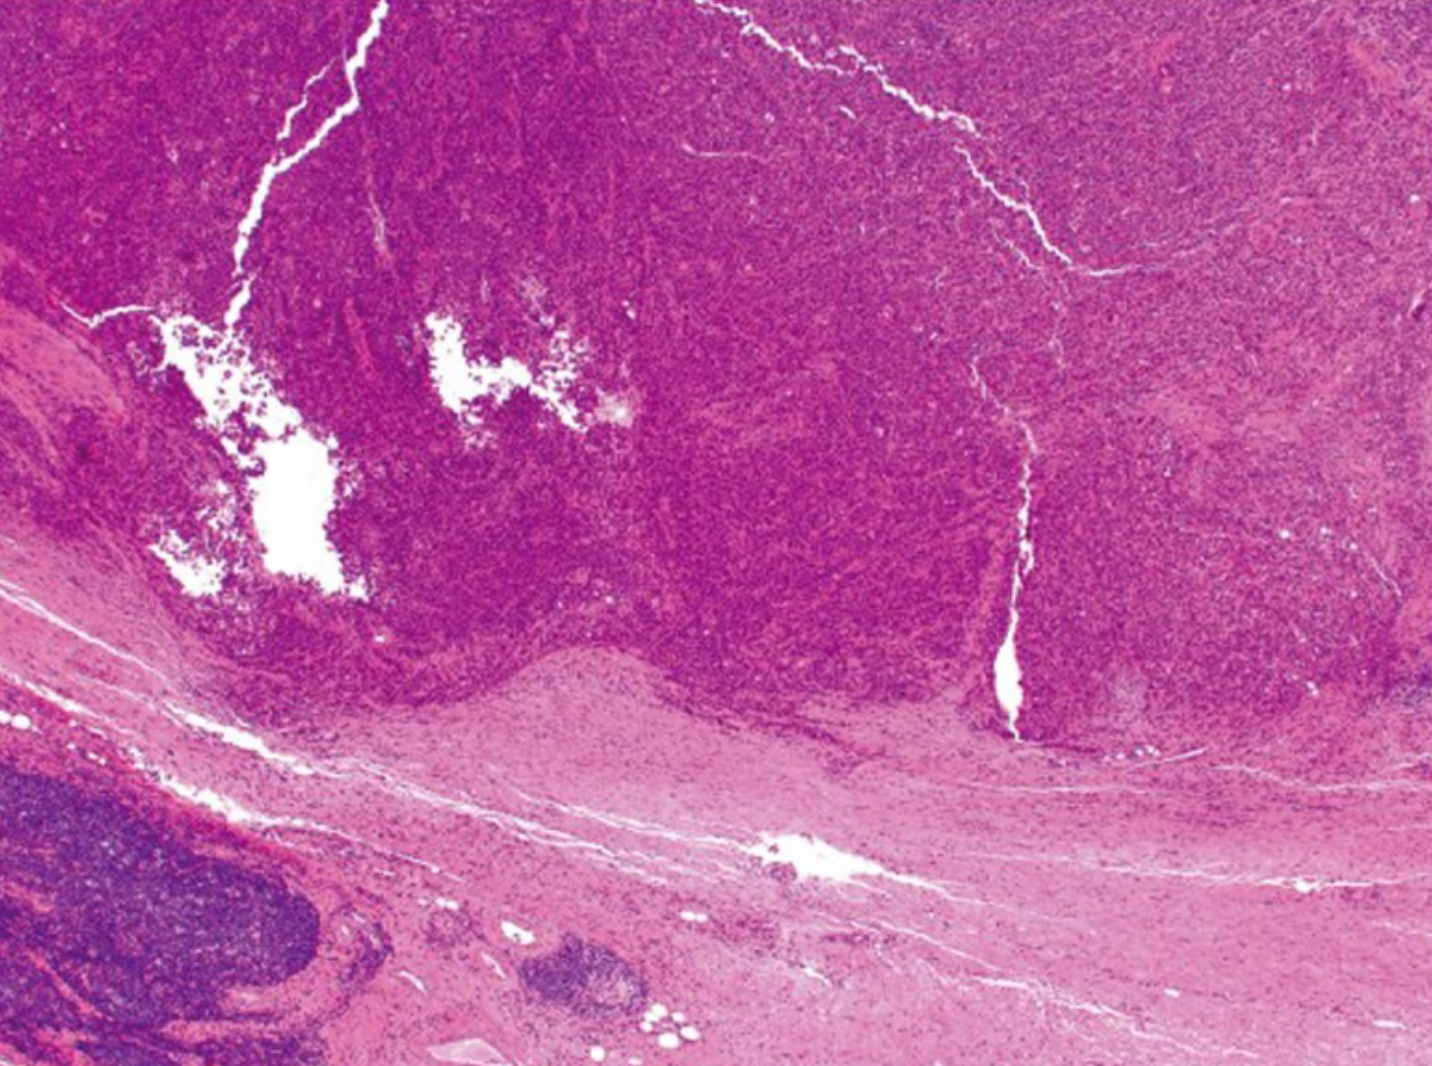

3.3髓样癌(Medullary carcinoma)

髓样癌极为罕见,每10000例结直肠癌确诊病例中约有5-8例。这种肿瘤的特征是上皮样肿瘤细胞片,具有大的泡状核,突出的核仁和丰富的细胞质。它通常在切除标本上有一个推动边界(图5),并且典型地与显著的肿瘤浸润淋巴细胞相关(图6)。髓样癌是一种独特的组织学亚型,尽管其组织学为低分化或未分化,但预后良好 [4]。

若本图无法展示,请更换浏览器查看

图5.髓样癌在肿瘤边缘呈推入性边界(原图×40)[4]。